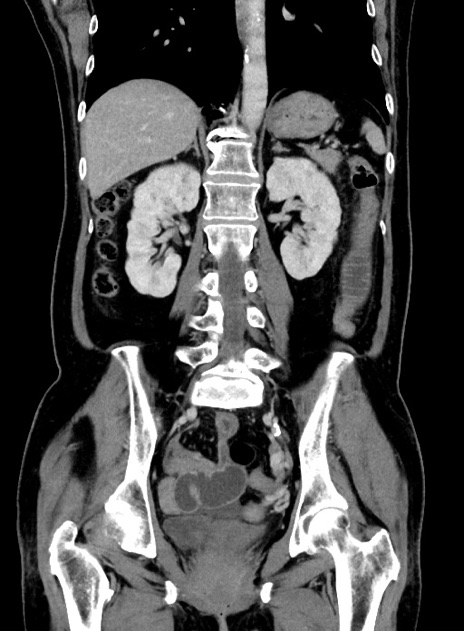

症例9(冠状断像)

【症例】 60歳代女性

【主訴】むかつき、みぞおちの痛み

【現病歴】3日前よりむかつきがあり、食事がとれない。

【既往歴】糖尿病

【身体所見】発熱なし、心窩部圧痛軽度あるも、腹膜刺激症状なし。

【データ】WBC 7400、CRP 1.92